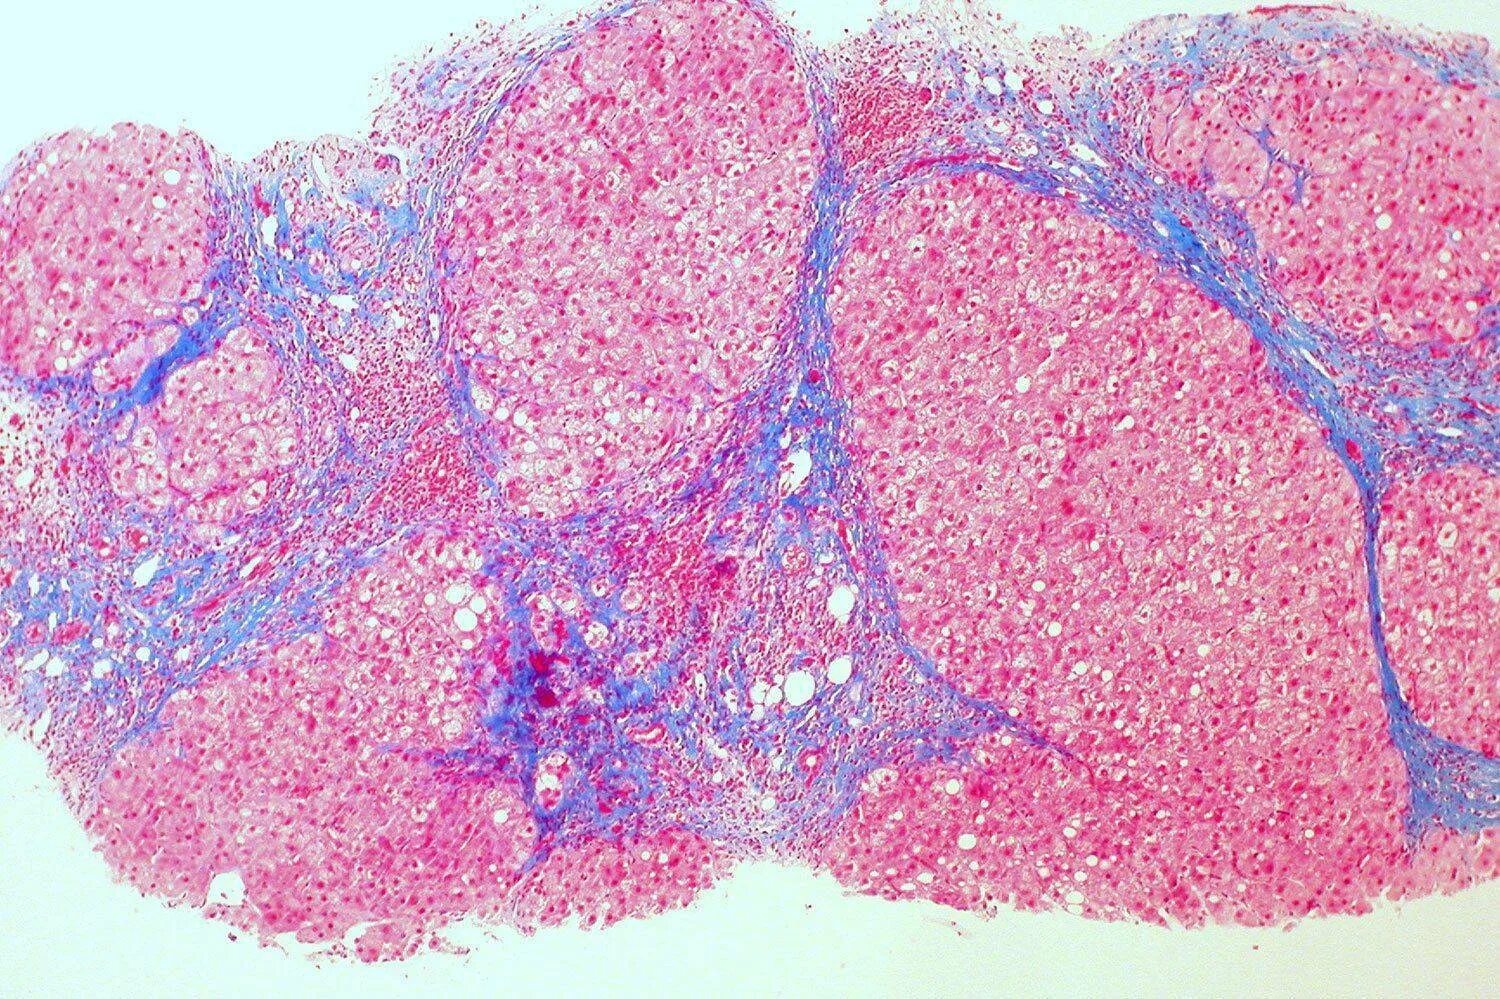

Узлы регенерации